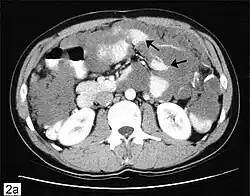

CT scanning is preferred to assess the extent of the tumor in the abdominopelvic cavity, though magnetic resonance imaging can also be used.[28] CT scanning can also be useful for finding omental caking or differentiating fluid from solid tumor in the abdomen, especially in low malignant potential tumors. However, it may not detect smaller tumors. Sometimes, a chest x-ray is used to detect metastases in the chest or pleural effusion. Another test for metastatic disease, though it is infrequently used, is a barium enema, which can show if the rectosigmoid colon is involved in the disease. Positron emission tomography, bone scans, and paracentesis are of limited use; in fact, paracentesis can cause metastases to form at the needle insertion site and may not provide useful results.[29] However, paracentesis can be used in cases where there is no pelvic mass and ascites is still present.[29] A physician suspecting ovarian cancer may also perform mammography or an endometrial biopsy (in the case of abnormal bleeding) to assess the possibility of breast malignancies and endometrial malignancy, respectively. Vaginal ultrasonography is often the first-line imaging study performed when an adnexal mass is found. Several characteristics of an adnexal mass indicate ovarian malignancy; they usually are solid, irregular, multilocular, and/or large; and they typically have papillary features, central vessels, and/or irregular internal septations.[31] However, SCST has no definitive characteristics on radiographic study.[32]